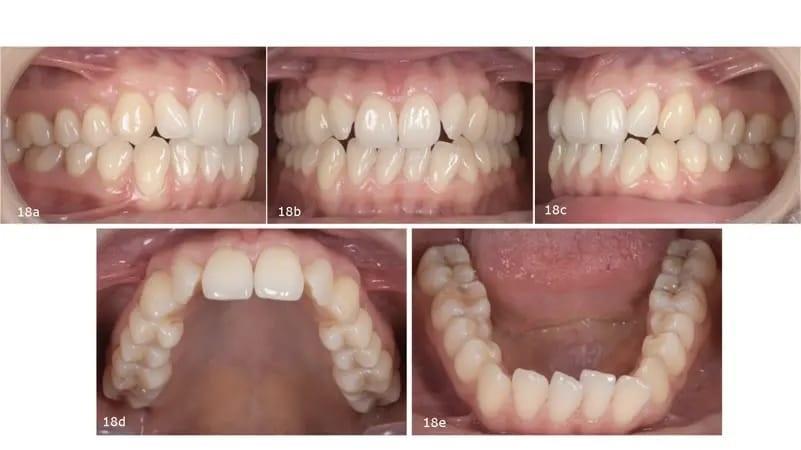

Окклюзионный анализ выявил неправильный прикус 2-го класса, а также тенденцию к переднему открытому прикусу, недостаточную подвижность и неправильный прикус, сужение верхней и нижнечелюстной области, отрицательный крутящий момент в обоих задних сегментах и на резцах верхней челюсти, слишком выраженная кривая Шпее и сильная скученность на обеих дугах. Средние линии зубов не были выровнены по центру. Средняя линия нижней челюсти отклонена влево, главным образом из-за наклона резцов нижней челюсти. Несмотря на благоприятный биотип десны и адекватное прилегание десны, у пациентки наблюдалась локализованная рецессия десны и абфракционные поражения — скорее всего, результат окклюзионной нестабильности и функциональной перегрузки (фото 18).

Фото 18a–e: Дооперационные интраоральные фотографии.